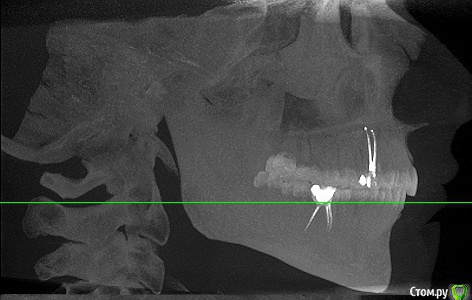

Прикрепляю не очень удачные скриншоты из КТ, которая была сделана через 4 дня после пломбировки каналов. К сожалению, других снимков на руках нет, только КТ.

post-58215-0-92104400-1563461580_thumb.jpg